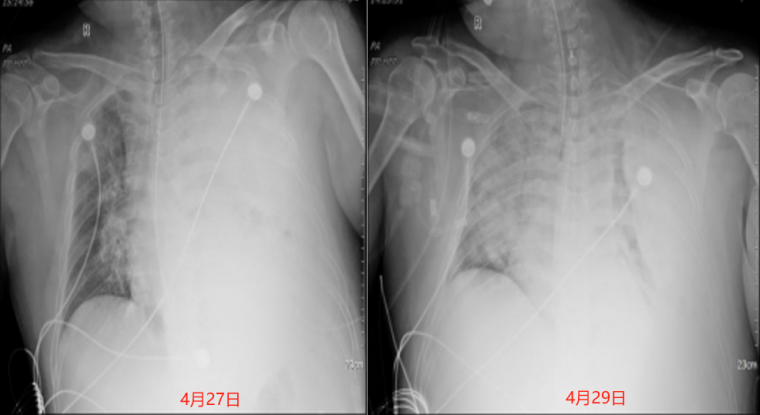

4月28日气管插管,4月29日患者氧合恶化PFR最低仅为58.3 mmHg(FiO2 100%)同时出现Ⅱ型呼吸衰竭(表1)患者体温较入院时有所好转(图3)4月29-30日复查感染指标,WBC(24.95×109/L)、PCT(1.53 ng/ml)、CRP(154.2 mg/L)较前整体呈下降趋势。4月29日复查胸部X线片:右肺渗出病灶较4月27日明显增多,左肺可见少许充气影(图4)考虑患者氧合恶化可能与右肺病灶增多有关

4  患者胸片变化